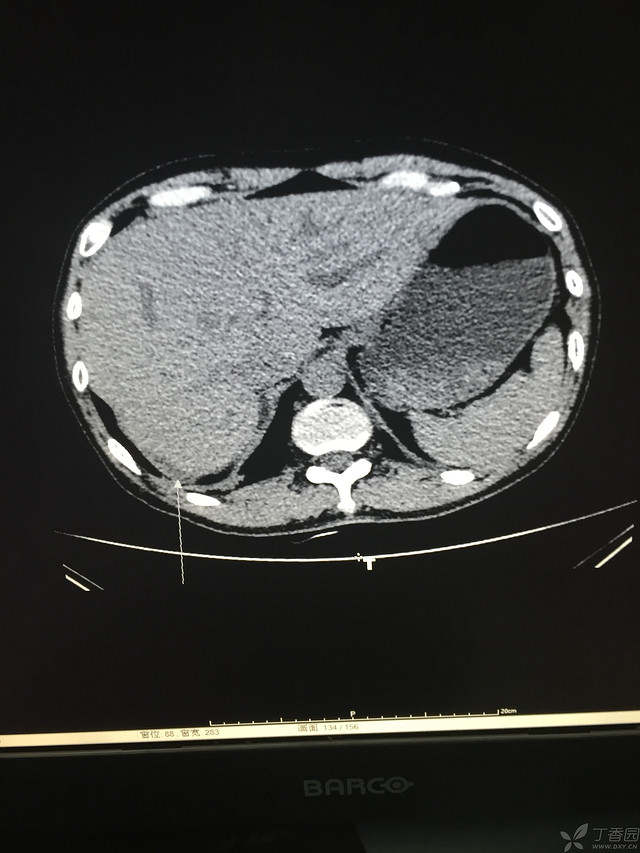

胸痛三天,加重三小时(CT是心包高密度影是什么)

患者性别:男

患者年龄:64岁

简要病史:三天前休息时突发胸前区疼痛伴大汗,到当地医院输液治疗后缓解,3小时前情绪激动后再次出现胸痛伴大汗,胸部压迫感,持续不缓解入院,到当地医院测血压180/?mmHg泵入硝酸甘油转入我院。

体格检查:血压94/72mmHg(右侧)96/74mmHg(左侧),心率78此/分,其他未见阳性体征